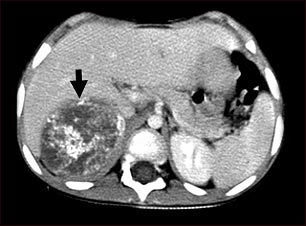

Tomografía computarizada de neuroblastoma en el hígado

Esta TC del abdomen superior muestra un tumor grande (neuroblastoma) en el lado derecho del abdomen del paciente (lado izquierdo inferior de la imagen). El tumor se encuentra detrás del hígado, empujándolo hacia adelante, y existe la posibilidad de que se disemine dentro del tejido hepático.